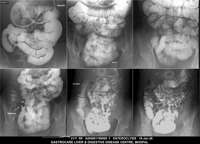

Section: ENTEROCLYSIS

Total: 205 Cases